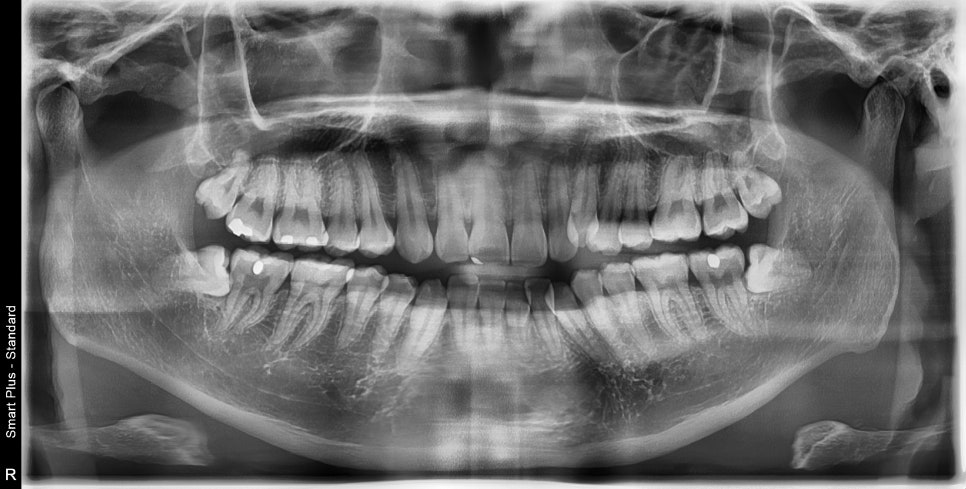

발치 교정으로 인비절라인 끝난 환자분으로

오른쪽은 그냥 돌출입의 교정

왼쪽은 덧니의 발치교정으로

좌 우를 보면 인비절라인과 관련된 모든 발치교정 이야기를 할 수 있을 것 같네요

위 2개는 3일전에 발치, 아래 두개는 인비절라인을 시작하는 날 발치하고 바로 장치를 착용했습니다.